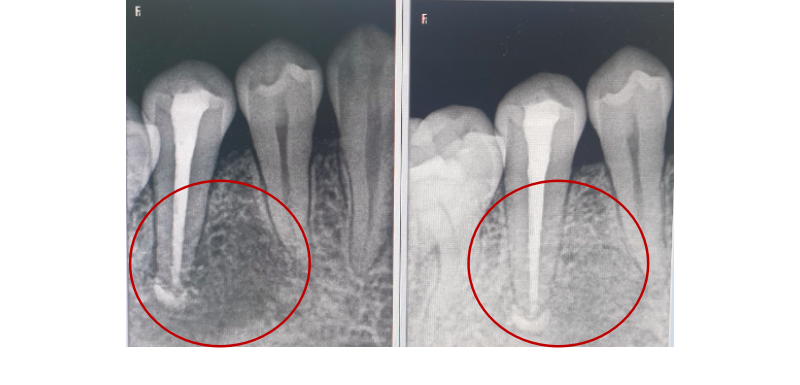

经过医生显微镜下细致操作,患者的患牙可以保留。(左图示下牙根尖区有阴影,经过手术后半年,右图示根尖区已经基本无阴影)

左图:

下牙根尖区有阴影

右图:

经过手术后半年,下牙根尖区已经基本无阴影